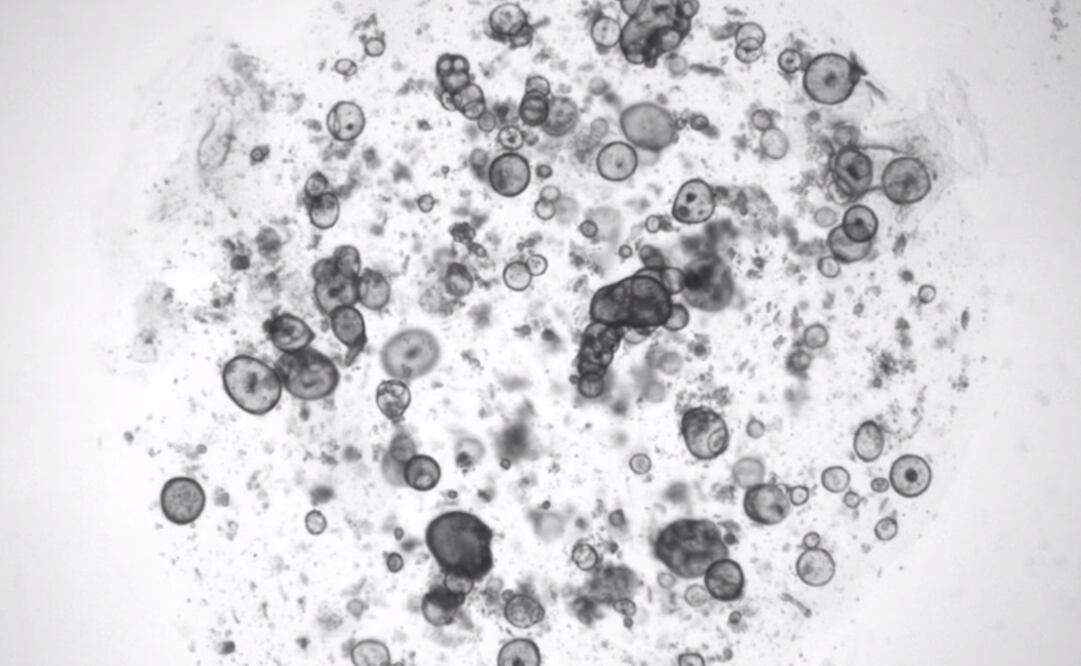

Foto: Marie Bannier-Hélaouët, Hubrecht Institute

Ante esta situación, los investigadores se basaron en experiencias previas para determinar las condiciones de cultivo de las células de las glándulas lagrimales humanas y de ratón. Posteriormente, se dedicaron a estimular la producción de lágrimas, para luego someter a los organoides a varias sustancias químicas, incluido el neurotransmisor norepinefrina, que transmite mensajes entre las células nerviosas y las glándulas.

Fue así que Clevers explicó que los organoides se hincharon durante la producción de lágrimas , ya que estos carecen de conductos como los que contiene las glándulas lagrimales reales: “Si hubiera habido un pequeño conducto, habría habido gotas”. Sin embargo, cuando el equipo trasplantó los organoides a ratones, los ensamblajes maduraron y desarrollaron estructuras similares a conductos que contienen proteínas que se encuentran en las lágrimas.